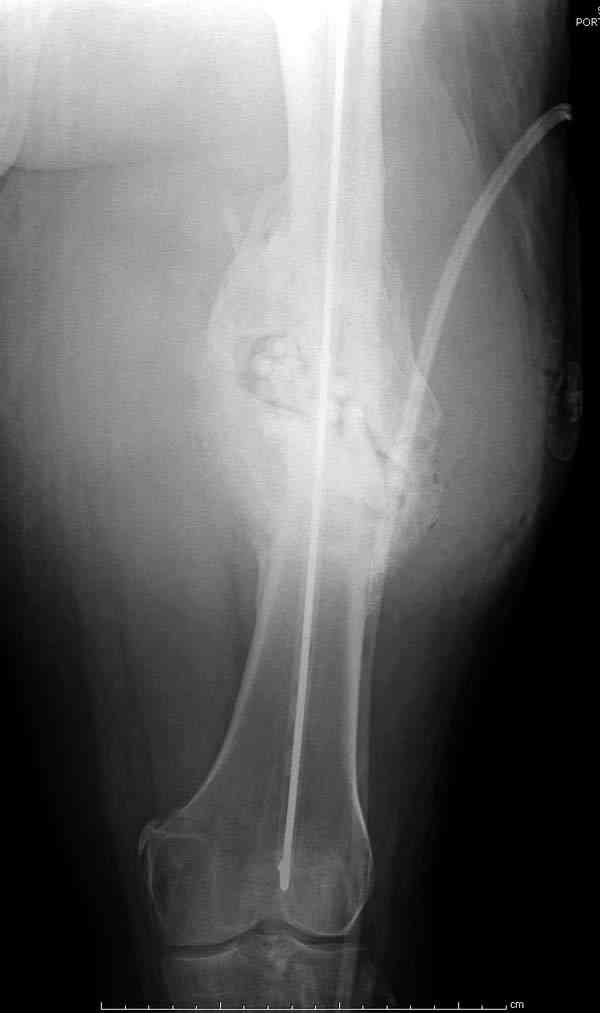

Недавний случай: год назад леченный интрамедуллярным гвоздем открытый перелом бедра инфецировался, многократные Irrigation&Debridment

закончили вставлением антибиотического гвоздя и кожной пластикой переднего мягкотканнего дефекта.

Редко, но бывает - недавно он обратился по поводу свищевого абцесса медиальной поверхности бедра.

На ренгенограмме явный остеомиелит с секвестром, секвестерэктомия из медиального доступа и замена старого антибиотического гвоздя на новый.

После трех дней ваккуумного дренажа, из латерального доступа удаление остатков старых антибиотичеких бус, закрытие медиальной раны с наложением ваккуумирования латерально. В следующий раз, через пару дней надеемся закрыть рану.

подготовка гвоздя

7-8 послеоперационные